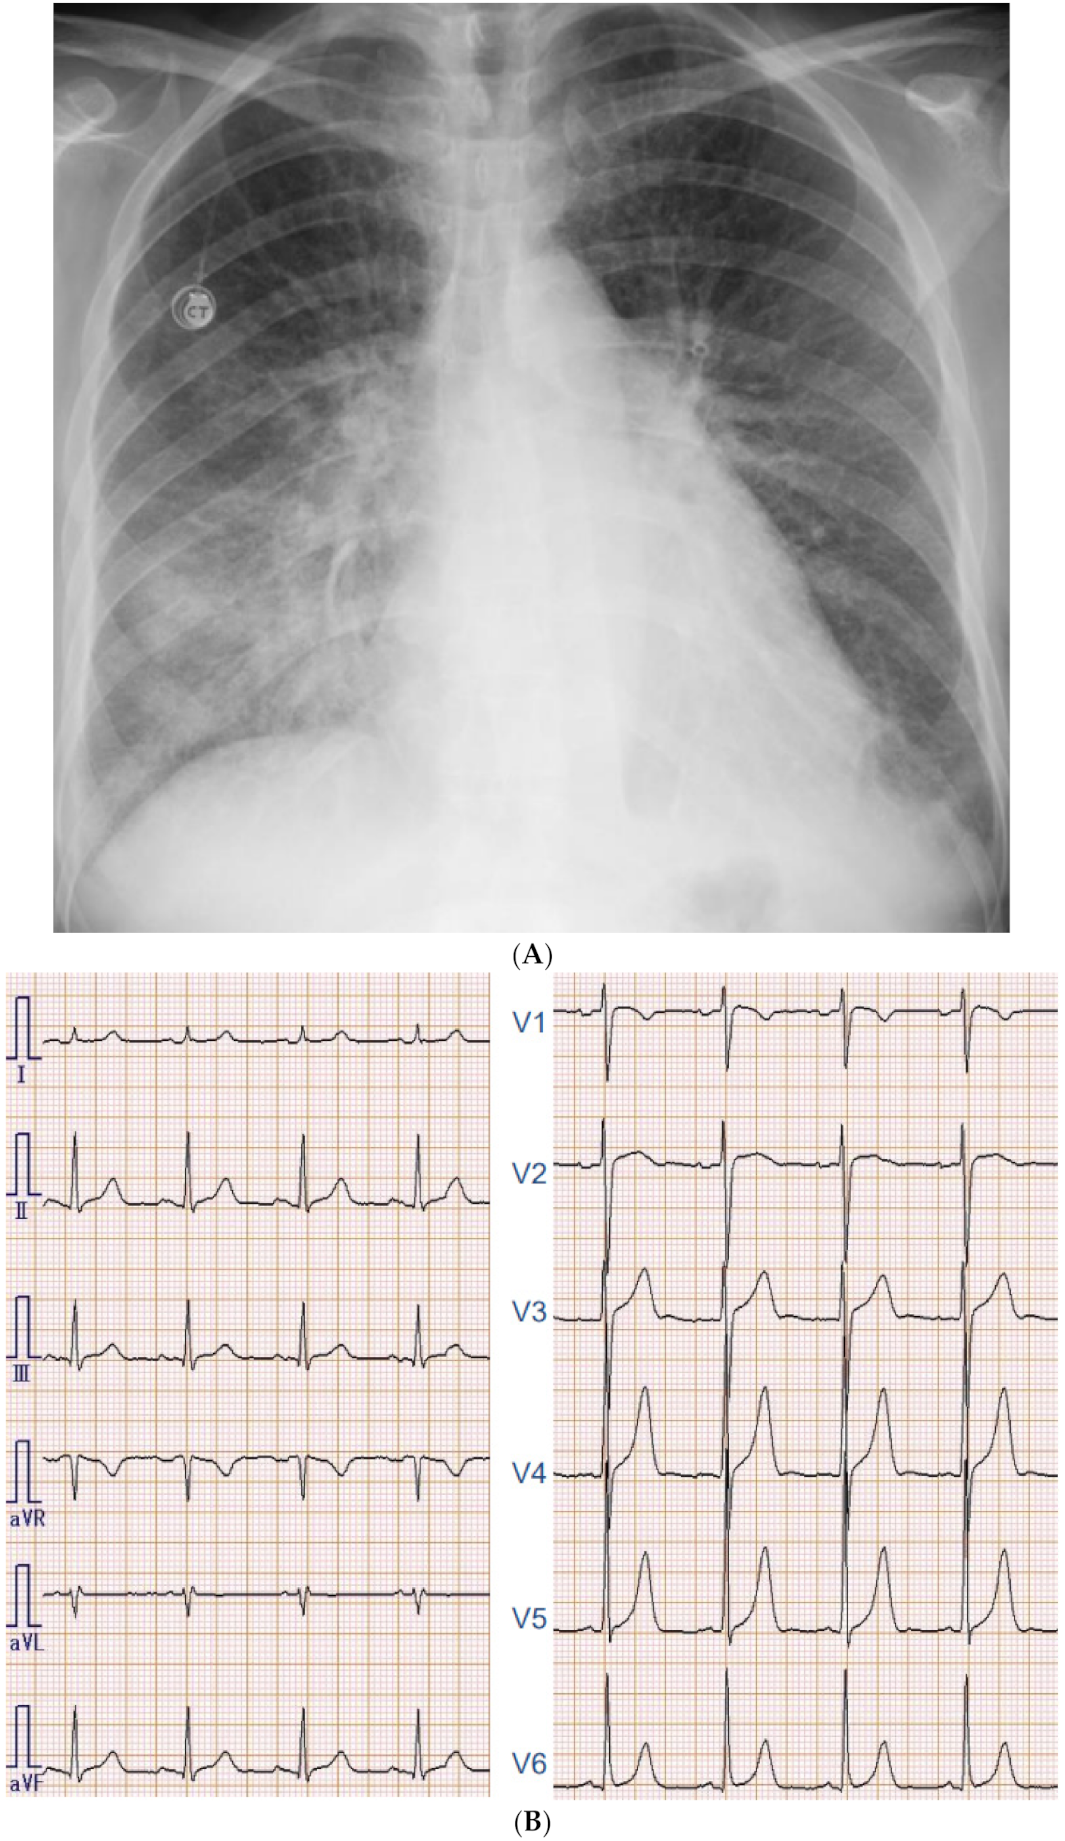

2.2. On Admission

2.3. In-Hospital Course